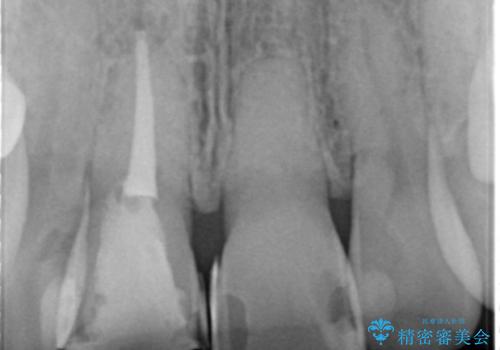

- 歯の神経を除去したのちの、変色の改善を希望され来院されました。

再度根管治療を行ったのちの、オールセラミッククラン治療を計画します。